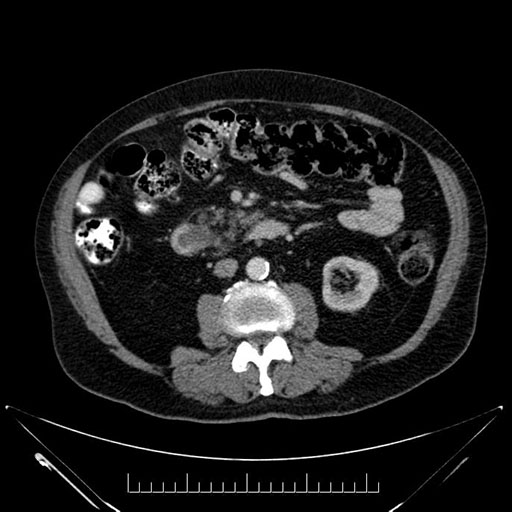

Axial - stented